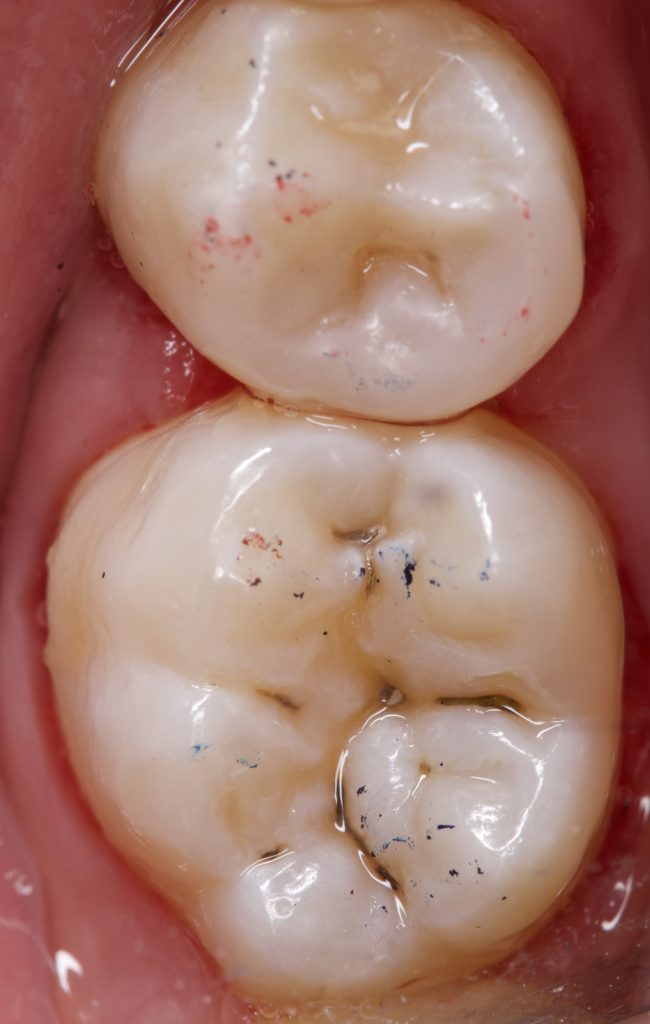

A patient presented with secondary caries under a defective restoration in the maxillary second premolar. The decay extended subgingivally, requiring deep margin management. Rubber dam isolation was applied to ensure a moisture-free environment and protect adjacent tissues during preparation.

The restoration achieved excellent proximal contact, anatomical accuracy, and high surface gloss. The combination of sandblasting, dual-flowable adaptation, fiber reinforcement, and FMT provided optimal biomechanics and esthetics.